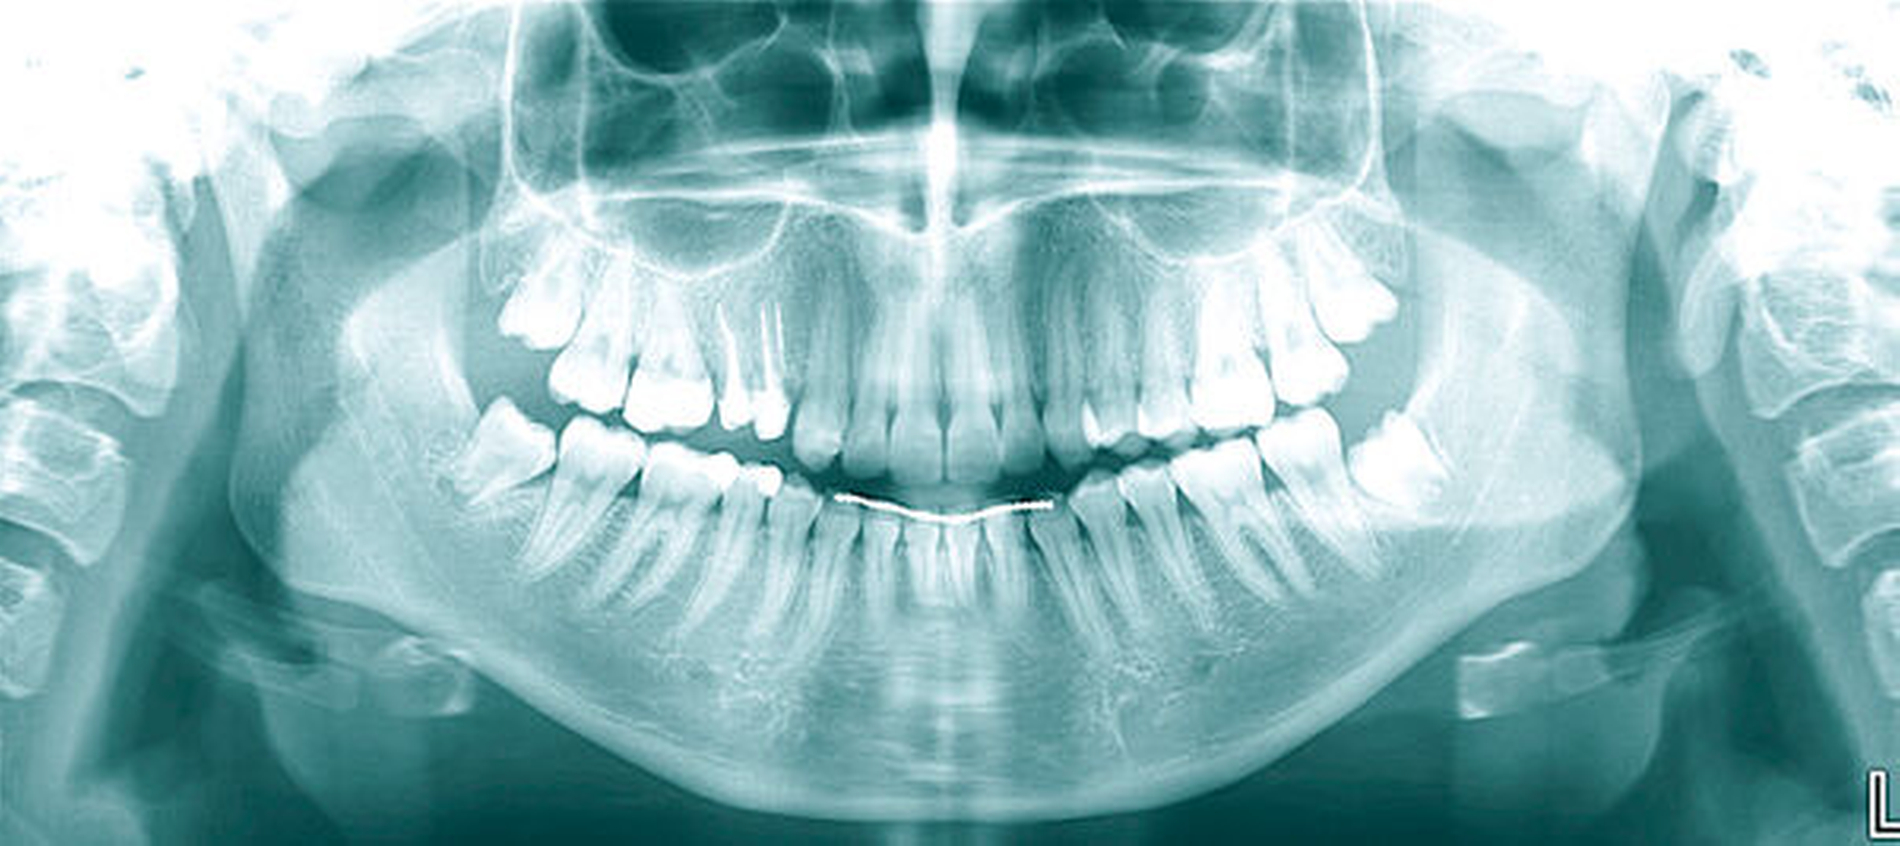

Auch bei scheinbar nicht optimalen Grundvoraussetzungen – wie einem zu erwartenden nicht ganz idealen Kronen-Wurzel-Verhältnis (1:1) – scheint die kieferothopädische Extrusion als Behandlungsoption nicht direkt ausgeschlossen werden zu müssen. Auf dem im Fall gezeigten OPG (Abbildung 9) stellen sich die Zahnwurzeln von 14 und 15 im kontralateralen Vergleich deutlich kürzer dar als die der Zähne 24 und 25. Die elektronische Messlänge bei der Revision der endodontischen Behandlung von Zahn 15 vor Eingliederung des Langzeitprovisoriums betrug lediglich 12 mm. Dennoch wiesen die Zähne 14 und 15 nach der Retentionsphase keine Lockerungsgrade auf, sodass die Autoren in der vermeintlich geringen Wurzellänge keine unbedingte Kontraindikation für das Ziel der Zahnerhaltung sehen. Auch wenn in diesem Fall die unterschiedliche Zahnlänge der Prämolaren im kontralateralen Vergleich klar mit der Extrusion der Zähne 14 und 15 zu erklären ist, stellen kieferorthopädische Bewegungen auch eine mögliche Ursache für die Verkürzung von Zahnwurzeln durch Resorptionen dar.